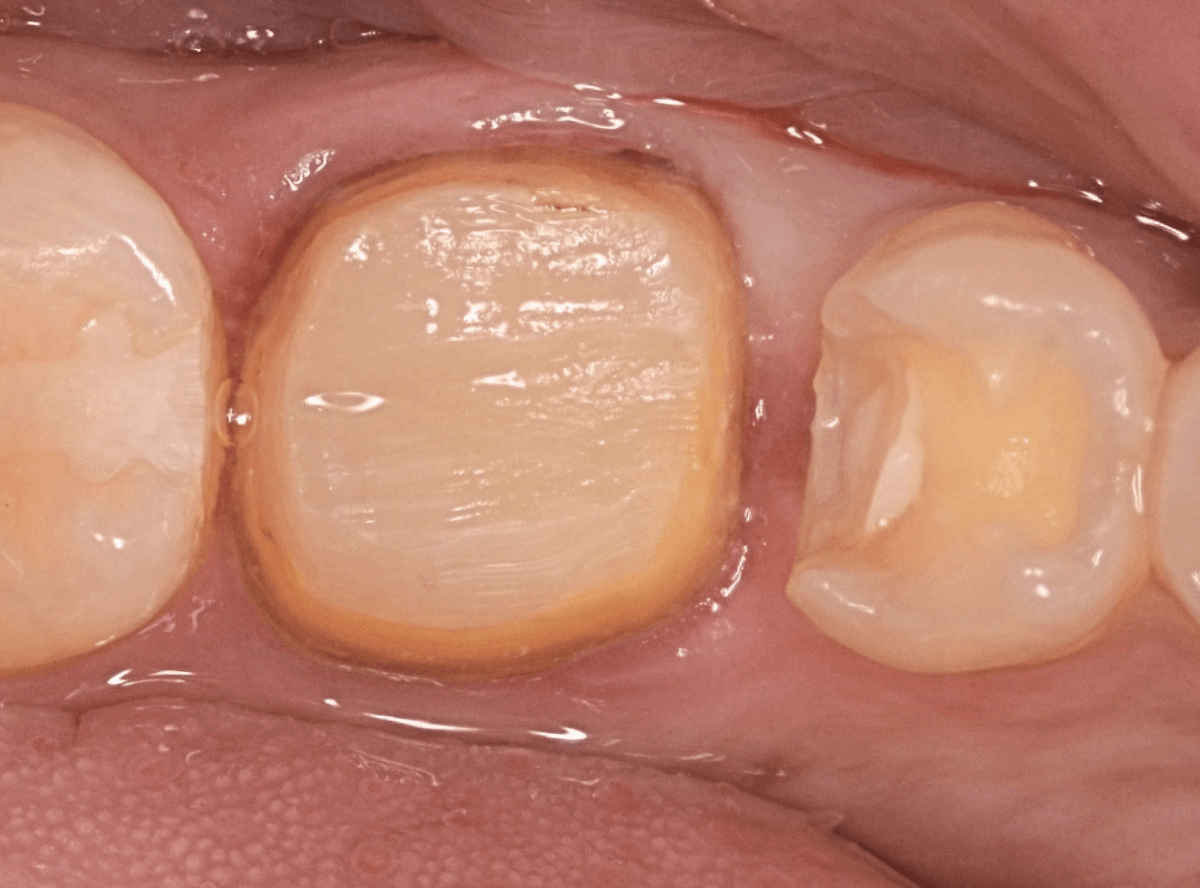

さし歯の土台の補修と、おやしらずの虫歯の処置をしたところです。

この状態で型をとります。